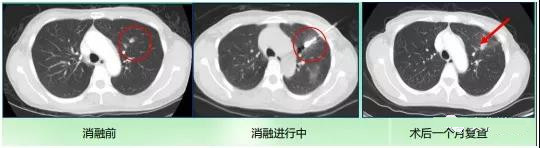

微波消融治疗肺癌,需在CT引导下,对肿瘤定位,并将消融针经皮穿刺植入病灶,利用 微波热效应,在短时间内使周围的组织温度升 高,使组织细胞蛋白质发生凝固性坏死,从而 达到根除或毁坏肿瘤的目的。治疗过程需要CT 监测,一般治疗时间在15-30分钟。

微波消融治疗术后对比

肺癌微波消融治疗效果